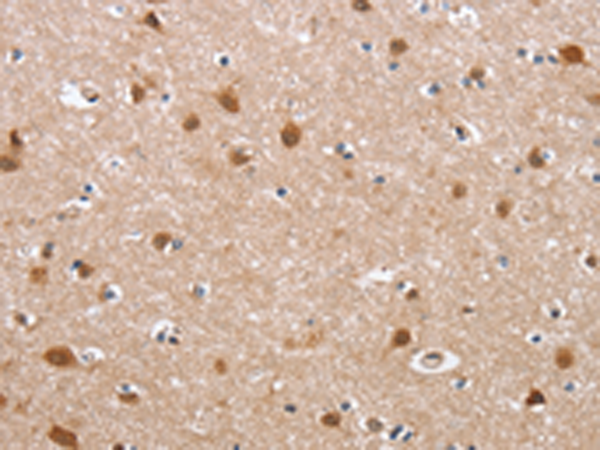

IHC positive control: |

Human brain |

IHC Recommend dilution: |

50-200 |